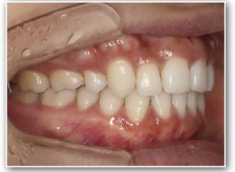

治療開始1年後